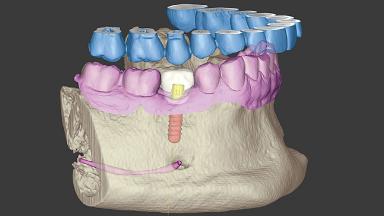

Replacing a Mandibular Second Premolar with a Chairside-Fabricated Crown

A 32-year-old male patient was referred to our department for a single-tooth replacement with an implant-supported crown. The patient was diagnosed with tooth agenesis at site 45 after extraction of the retained deciduous tooth (85, primary second molar) by his general practitioner. At baseline, the full-mouth plaque score (PI) was 21%; probing pocket depths (PPD) ranged from 1 to 3 mm, and bleeding on probing (BoP) was 17%.